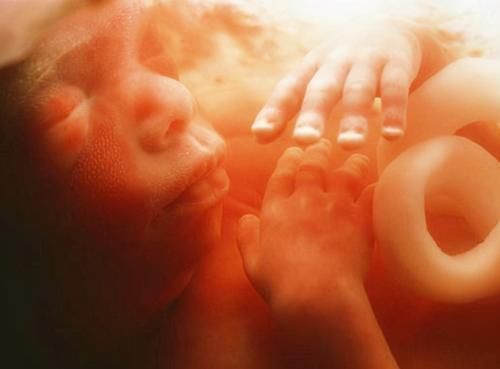

别以为是宝宝天生就丑,事实上再好看的娃,在羊水里泡那么久也变得难看了。而且这个时候他们大多都是闭着眼睛,五官都还没有完全长开,所以拍出来丑一点也是情有可原的。

文章插图